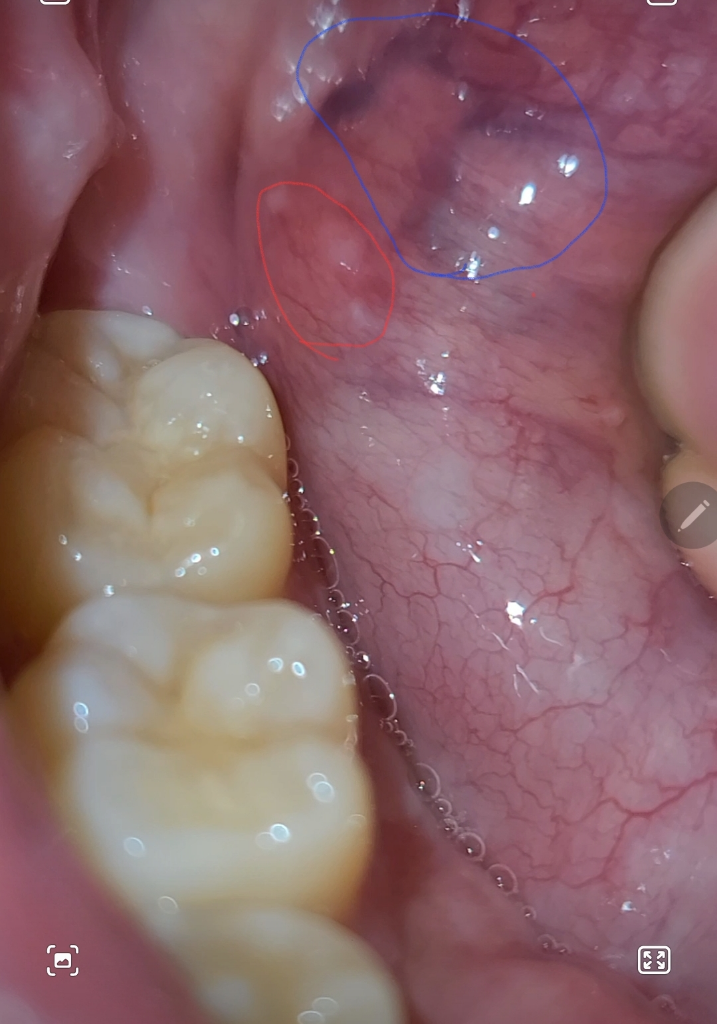

구강에 하얀것이 2주넘게안없어지는데 구강암일까요??

1.빨간색부분이 2주넘게 안없어지네요ㅠㅠ 아프타치도 붙여보고 알보칠도발라봤는데 안없어지네요ㅠㅠ

동네병원 3곳 가봤는데 두곳은 정상구조물이라고하고 한곳은 헐은거라고하던데 말이 달라서요ㅜㅜ

구강암일 확률이 높을까요ㅠㅠ 20대중반 술담배안해요

2.파란색부분은 왤케검은건가요ㅠㅠ 정상적인걸까요??

파란색부분은 혈관이 보이는거고 튀어나온건 자극을 받아서 잇몸이 튀어나온것같습니다. 크게 걱정은 안하셔도 될것같습니다.

구강암일 가능성은 낮으며, 피로및 스트레스로인한 구내염일 가능성이 높습니다. 충분한 휴식과 비타민섭취를 하면서 1달정도 지켜보길 권하며, 통증 및 붓기가 없는 경우에는 문제가 되지 않습니다.